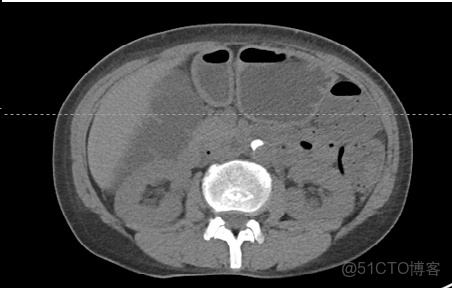

腹部窗口窗口設置: (W:400,L:40)優點: 顧名思義,該窗口用於評估腹腔及其內容物。接近流體/軟組織的窗口水平與中等大小的窗口一起使用,可提供中等程度的對比度。

CLAHE算法增強局部對比度的X光圖像增強效果對比_ico_11

腹窗可用於評估腹腔內的病變。